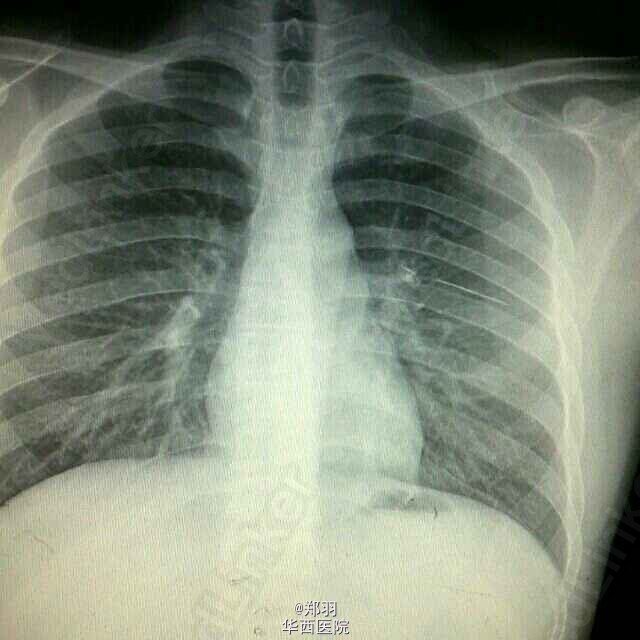

患者,男,24岁,体检发现左肺上叶异物1+月。无任何其他不适。

胸部平片及胸部CT平扫提示左肺上叶有一细条状金属异物。纤支镜提示左肺支气管分叉处有瘢痕,为金属异物从后背刺入肺内,并深入支气管,因为术中发现后方胸膜有粘连。

讨论后行胸腔镜左肺上叶切除。

这个异物到底怎么处置呢?主要考虑到为一个没有任何症状的异物,切掉一叶肺,且患者很年轻,有些可惜。但是异物有刺破血管的风险,容易导致慢性咯血或者大出血,不倾向保守治疗。但考虑到支气管的瘢痕灶,影响术后吻合支气管愈合,经讨论决定扩大切除范围,所以切掉左肺上叶。